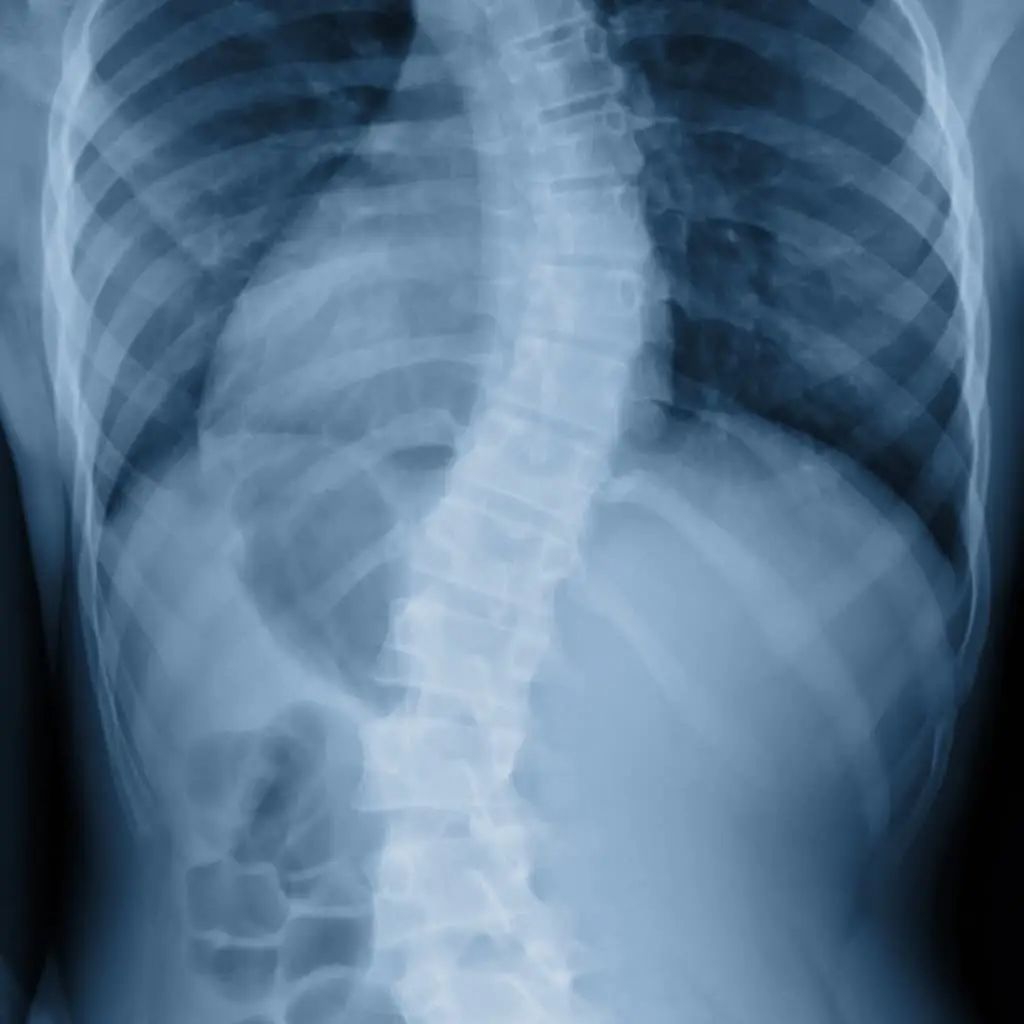

Spine Conditions

We help diagnose and treat spine issues that affect your comfort, movement, and daily life—offering personalised care to support long-term recovery and relief.

- Lower back pain, upper back pain, neck pain

- Curved spine (scoliosis and kyphosis)